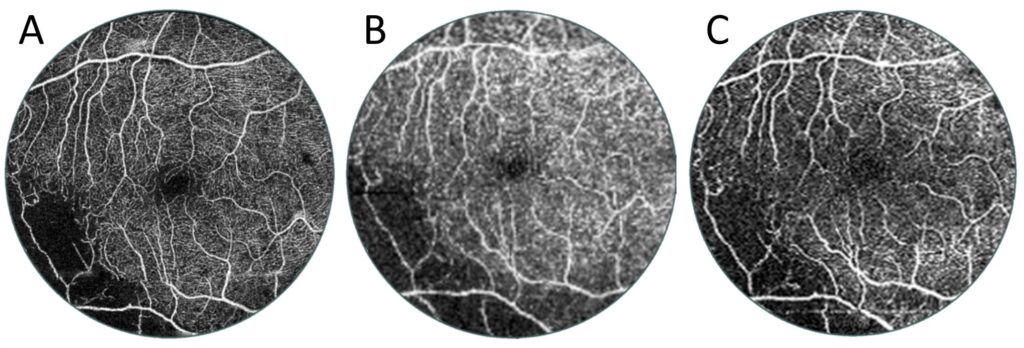

Figure 9 shows a case of a patient with branch retinal vein occlusion. A typical 6 × 6 mm scan shows an area of non-perfusion in the lower left of the image. This information enables a diagnosis but not treatment (e.g., in the form of laser therapy). A 15 × 15 mm widefield scan taken without an additional lens, which is the widest possible on the device, shows a slightly larger no-flow area. In contrast, the UWF scan clearly detects extensive ischaemia. This is clinically useful information, as it can be used to guide laser therapy. These angiograms can also be analysed from another perspective. Figure 10 shows a comparison of exactly the same area from scans of different widths of the patient shown in Figure 9. In the case of the 6 × 6 mm scan, this is the entire image, and in the case of the other two scans, it is their central 6 × 6 mm portion. It can be seen that the quality of the routine 6 × 6 mm measurement is slightly higher, but the UWF scan also carries all clinically important information of this area. It allows the boundaries of the zones of non-perfusion in the centre of the posterior pole to be traced and allows an overall vascular assessment of the macula to be performed.

Figure 9. OCT angiography of a patient with branch retinal vein occlusion (female, age 46). (A) Measurement with a scan area of 6 × 6 mm. (B) Angiography taken over an area of 15 × 15 mm. (C) UWF OCT angiography covering an area 22 mm in diameter.

Figure 10. Comparison of the same size central 6 × 6 mm area of different-sized OCT angiographies of the patient in Figure 9. (A) Reference OCT angiography of 6 mm diameter. (B) The central area of the OCT examination with a width of 15 mm. This angio-OCT examination has a lower scanning density and hence lower quality than the other two images. (C) Enlarged UWF OCT centre of angiography taken with a diameter of 22 mm.